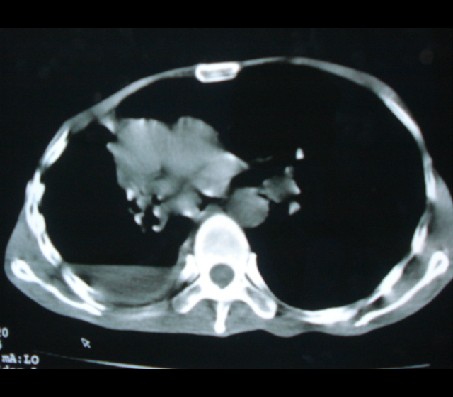

标题: CT17018:肺脓肿?左侧胸腔积液?请会诊! [打印本页]

标题: CT17018:肺脓肿?左侧胸腔积液?请会诊!

男性,65岁,有肺结核病史。

1)两肺继发性肺结核伴右肺毁损,右肺多发空洞及肺大泡形成并感染,伴左肺支气管播散。右侧液气胸.2)右侧胸膜增厚、粘连。3)纵隔疝(左→右)。

液气胸,毁损肺。老结核,纵隔疝。

纵隔疝。